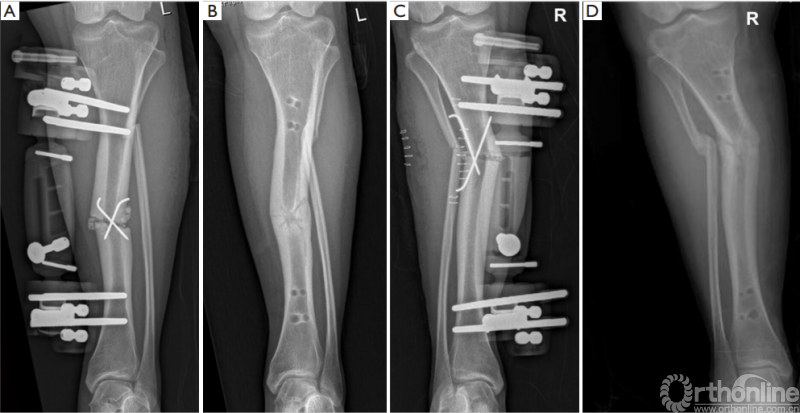

矫正后的双侧力线较术前均明显改善(表 2) 。在最后一次就诊时,PPTA和ADTA接近正常值,得到了明显的矫正(图 4C,D, 表 2) 。在上次访问中,双侧骨质均已愈合(图 5) 。

图5 术后影像学随访提示骨愈合。(A)左下肢术后X线;(B)术后11个月骨愈合;(C)右下肢术后X线;(D)术后13个月右侧骨愈合。

直到最近一次随访,膝关节踝关节的活动度都与术前一致。从初次手术到完全负重的时间为3个月。无疼痛或其他并发症,如神经损伤、骨筋膜室综合征、髌骨低位、骨髓炎、延迟创面愈合、针道感染等。